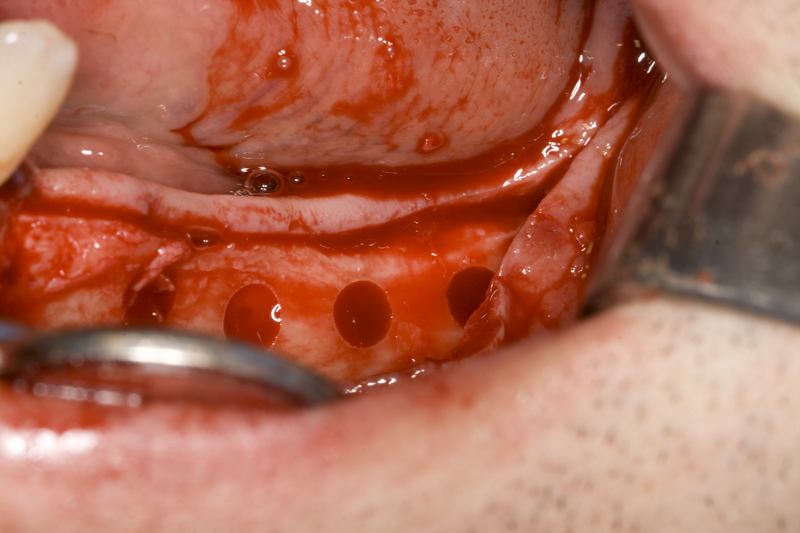

При операции с цел изграждане на допълнителн костна тъкан (костна пластика) винаги е добре да се перфорира кортикалната пластинка на костта. През тези перфорации излизат костни клетки, които постепенно прорастват в котозаместващия материал и синтезират нова костна тъкан. Перфорациите могат да се извършат с кръгло борче или с АСМ - фрезата на Neobiotech - Южна Корея.

С фрезата за автогенна кост се извършва много бързо и лесно отнемане на

кортикалната кост